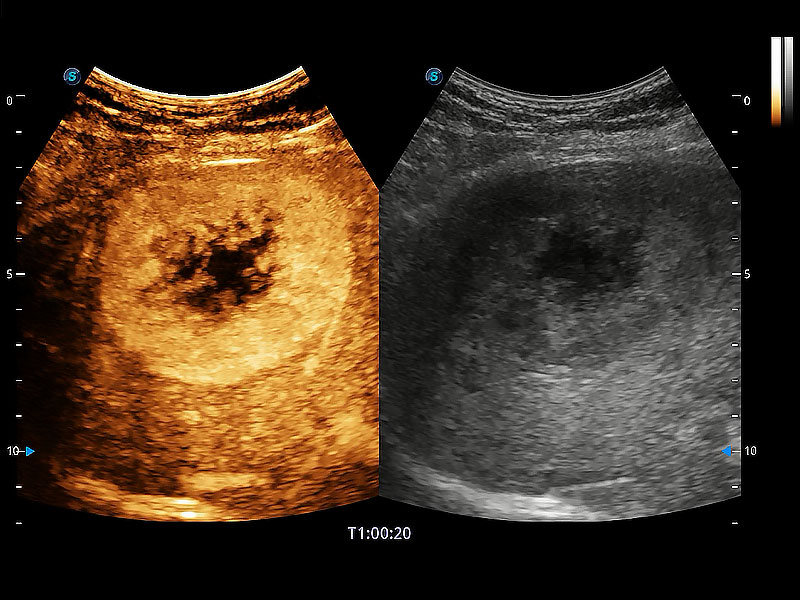

优异的基础图像

ProPet 80 全新的动物超声智能软件和丰富的探头群,为动物医生提供了高清晰度和精细分辨率的图像,无论在宠物、马科、畜牧还是实验室动物等应用中都可以轻松应对,为您的日常工作带来满意的体验。

(犬)肝脏

(猫)胆囊